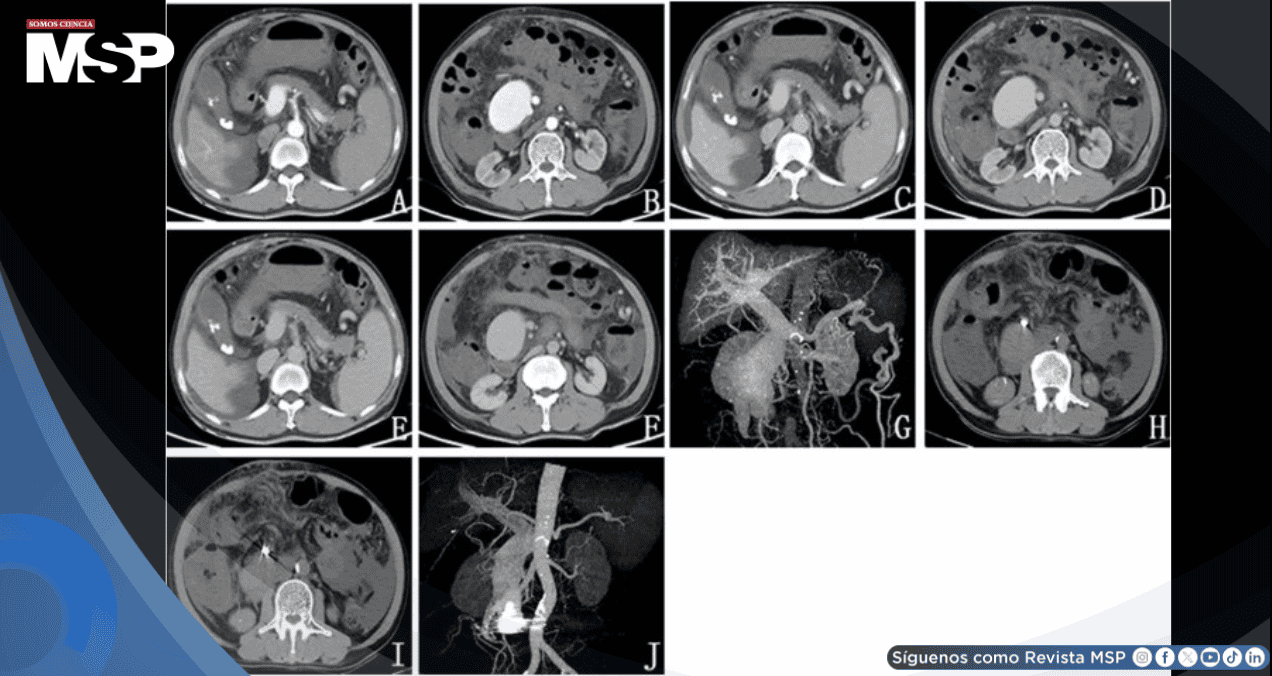

Los estudios de imagen realizados fueron determinantes para establecer el diagnóstico. La tomografía computarizada contrastada del abdomen superior junto con la venografía por tomografía de la vena porta demostraron hallazgos compatibles con cirrosis hepática establecida y esplenomegalia.

Sumado a eso, se identificó hipertensión portal con formación de extensa circulación colateral que comprometía el esófago, el fondo gástrico y la pared abdominal. Un hallazgo particularmente llamativo fue la dilatación de aspecto tumoral de la vena mesentérica superior, acompañada de formación de ascitis.

La cavografía de vena cava inferior y la arteriografía celíaca permitieron confirmar el diagnóstico definitivo de fístula arteriovenosa mesentérica superior de origen postraumático, estableciendo una relación directa con el accidente sufrido años atrás.